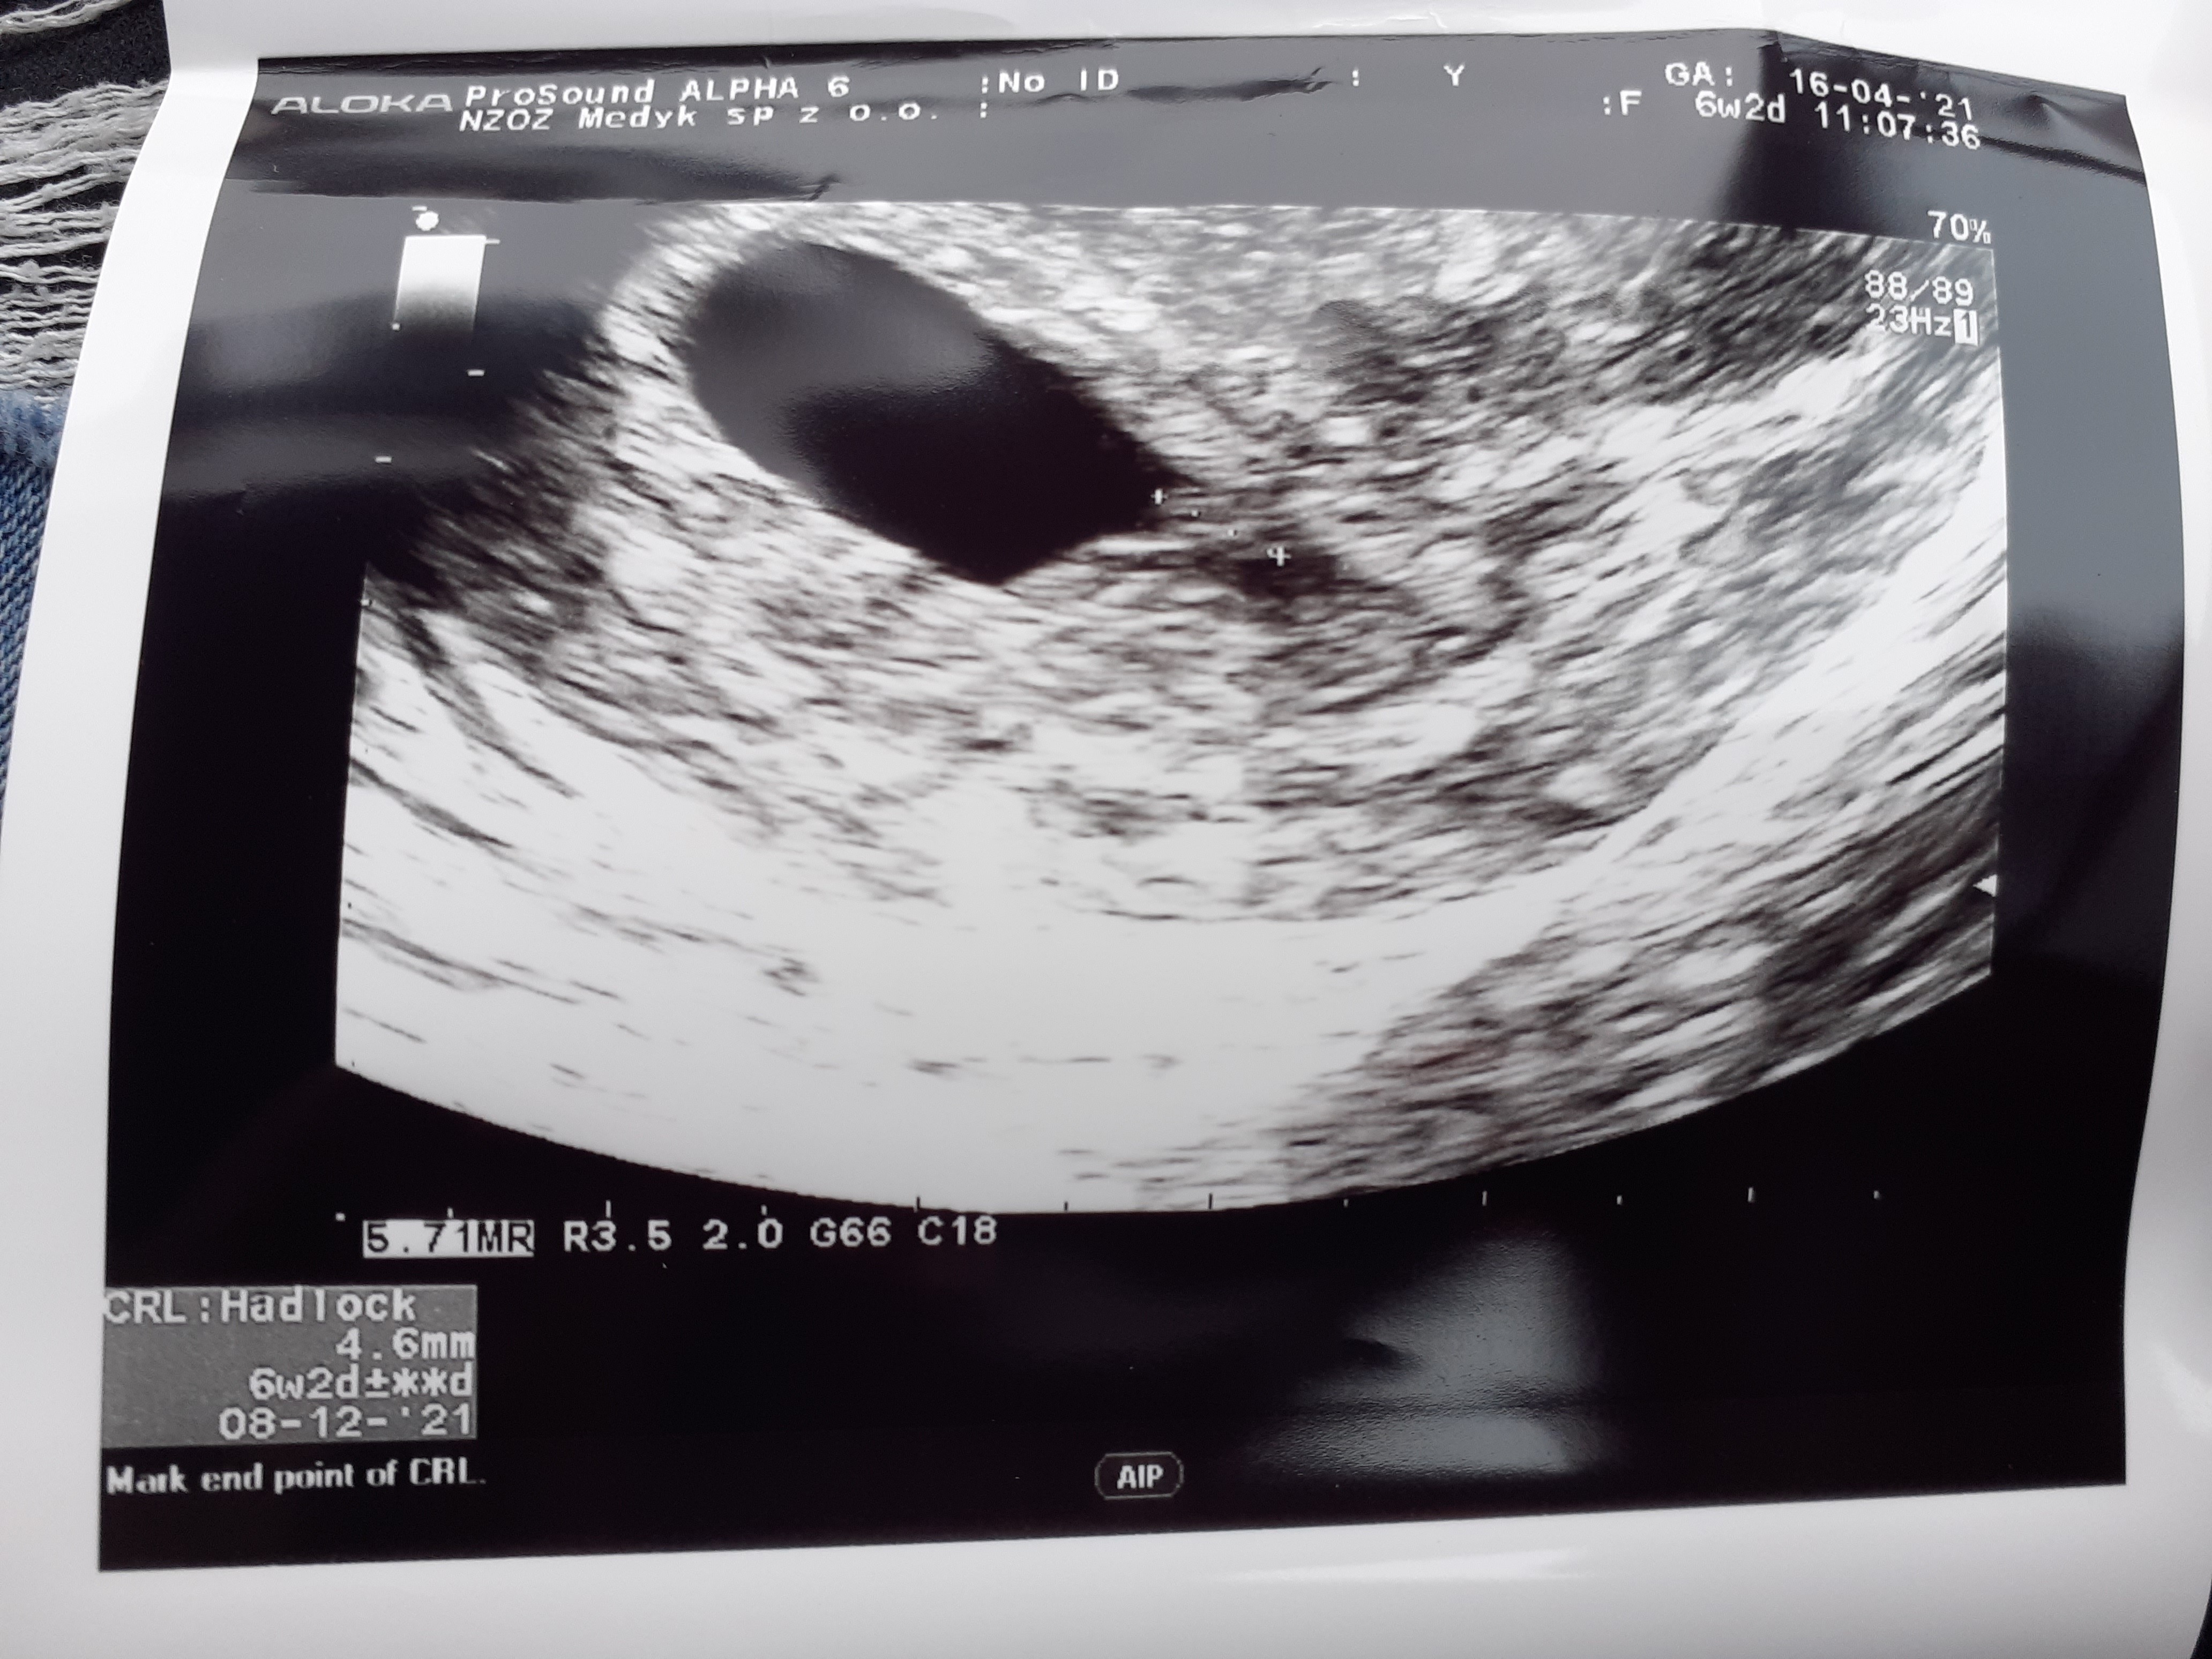

Po wizycie w szpitalu dzisiaj miałam kontrolę u swojego lekarza. Ciąża okazała się młodsza. Po wielkim stresie pokazał się nareszcie zarodek👌🏻Serca nie było słychać ale pokazał mi coś jakby obraz bicia. W 4+2 nie było pęcherzyka, w 5+2 do 5+6 był pęcherzyk, ale nie było zarodka, w 6+2 jest zarodek. Widocznie jest młodszy niż pokazuje OM.

Załączniki

• 20210416_134257.jpg

20210416_134257.jpg

1,7 MB · Wyświetleń: 93